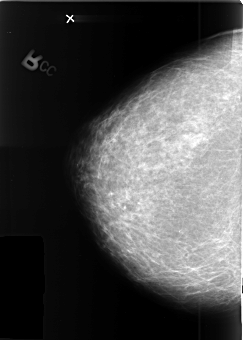

B_3410_1.RIGHT_CC

LEFT_CC LINES 4176 PIXELS_PER_LINE 2776 BITS_PER_PIXEL 12 RESOLUTION 50 OVERLAY

FILE: B_3410_1.LEFT_CC.OVERLAY

TOTAL_ABNORMALITIES 1

ABNORMALITY 1

LESION_TYPE MASS SHAPE ROUND MARGINS OBSCURED

ASSESSMENT 3

SUBTLETY 5

PATHOLOGY MALIGNANT

TOTAL_OUTLINES 1

BOUNDARY